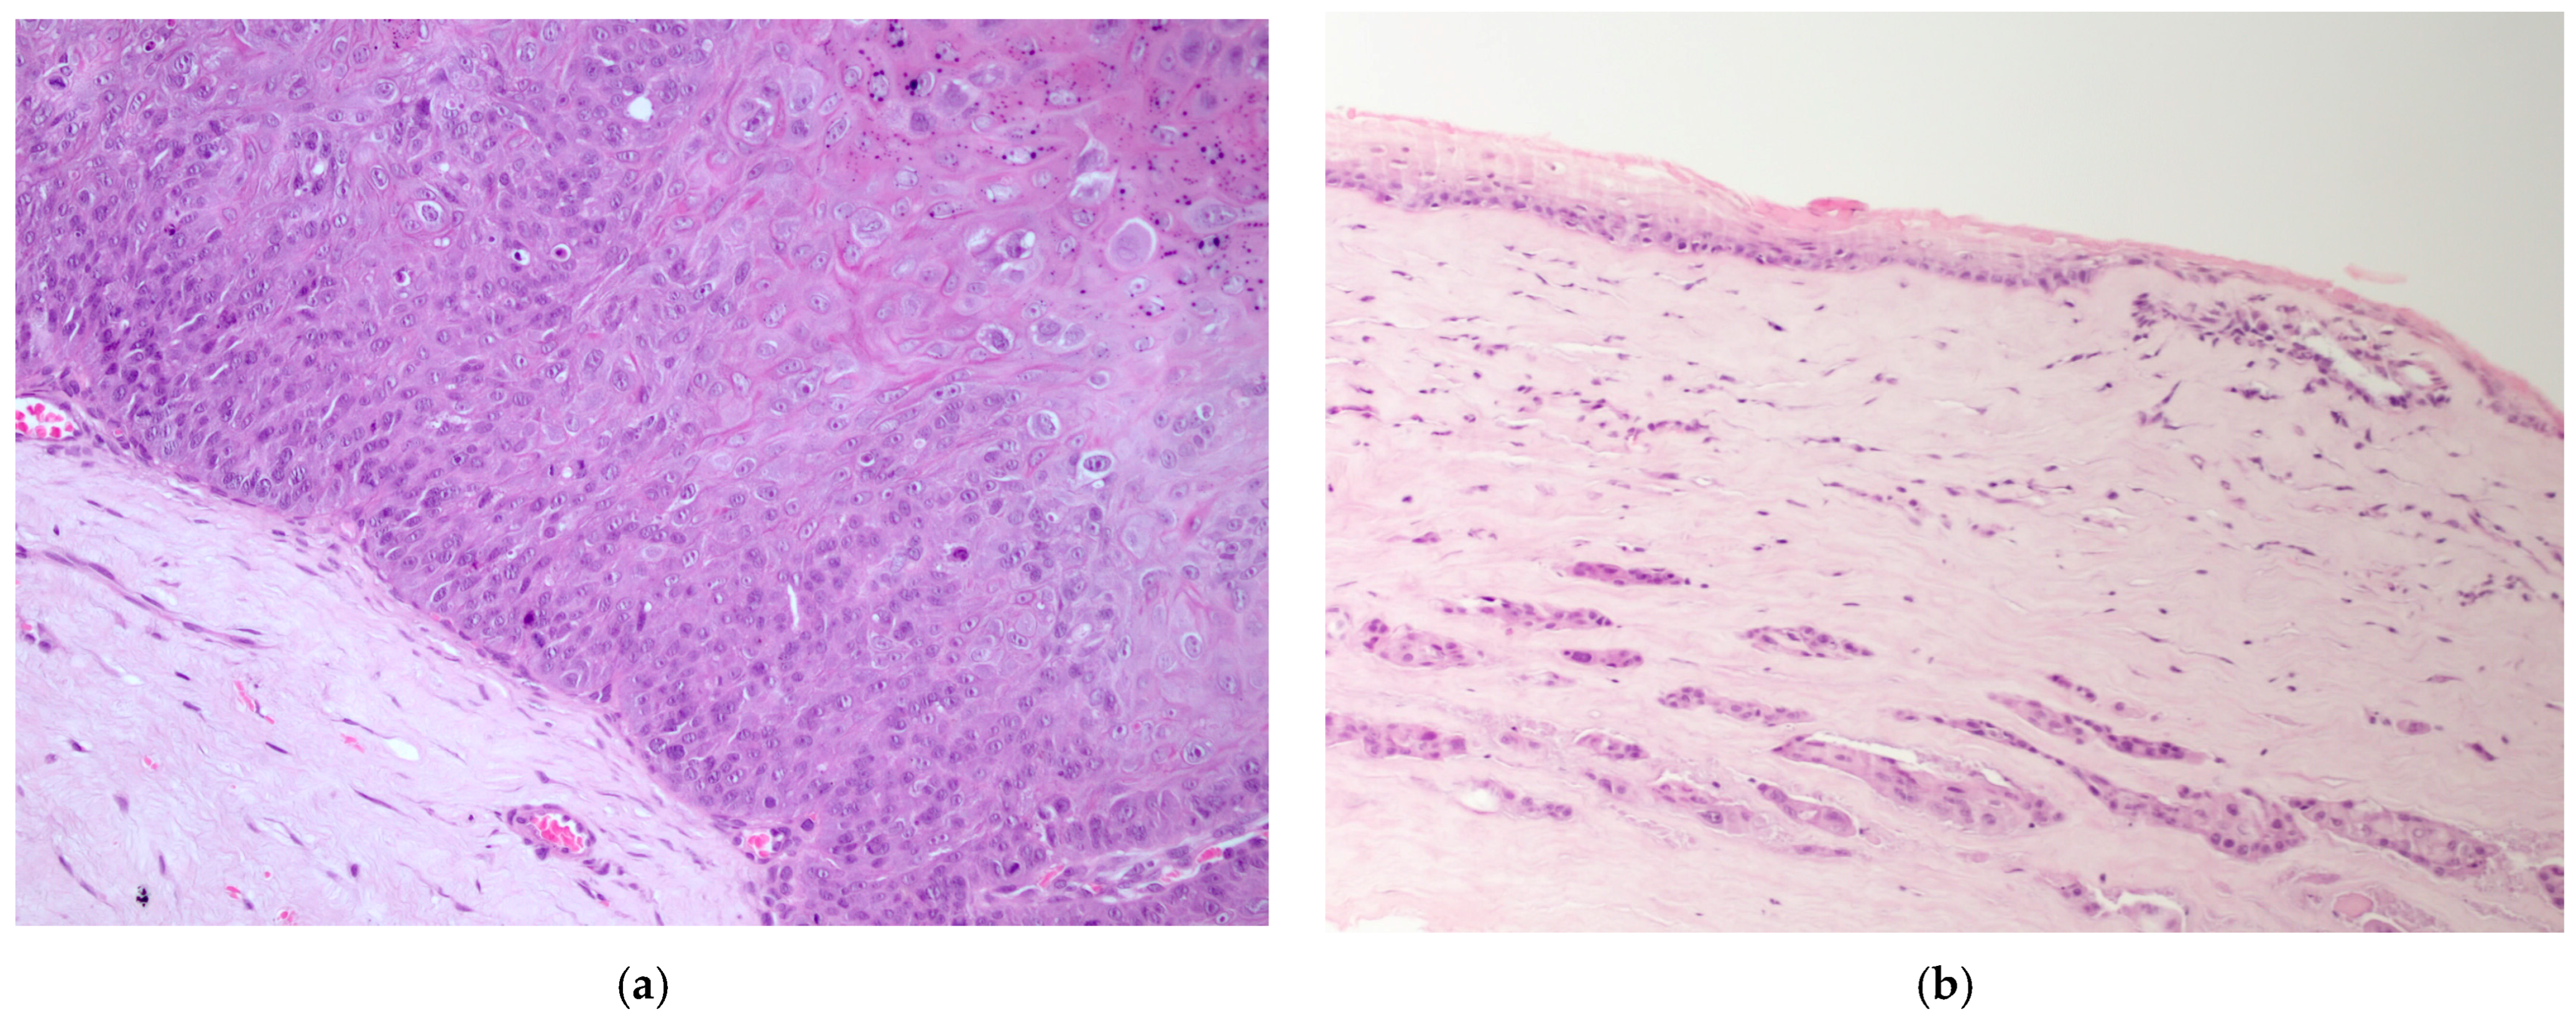

The majority of epithelial neoplasia were SCC (38/41), 2/41 were papillomas, one of which had focal transformation into in situ SCC. All c-SCC and papillomas grew in the central cornea, variably extending to the limbus (Figure 1a,b), except one papilloma with histopathological signs of viral infection, which primarily arose on the limbus (Figure 2a).

Figure 1.

(a) Dog, eye globe, macroscopic picture of cross-section: a large exophytic c-SCC affects the entire surface of the cornea, extending focally to the limbus; (b) dog, eye globe: histological subgross view of a typical exophytic c-SCC, not infiltrating the deeper corneal stroma (EE, 4×).

Figure 2.

(a) Dog, corneal biopsy: corneo-limbal papilloma with scattered koilocytes, suggesting a viral origin (EE, 10×); (b) dog, corneal biopsy: neoplastic cells grow into the corneal stroma apparently without connection with the surface epithelium (stromal invasive pattern) (EE, 10×).

c-SCCs mostly grew as exophytic masses with limited infiltration into the corneal stroma (24/38). In only 8/38 cases, infiltrative growth into the stroma was pronounced; of these, 2/8 cases showed a “stromal invasive pattern”, forming islands of neoplastic cells that dissected the corneal stroma, while the overlaying corneal epithelium was apparently unaffected (Figure 2b). Six cases were in situ SCC (6/38). In one case, neoplastic cells were focally arranged in a pseudoacinar pattern.